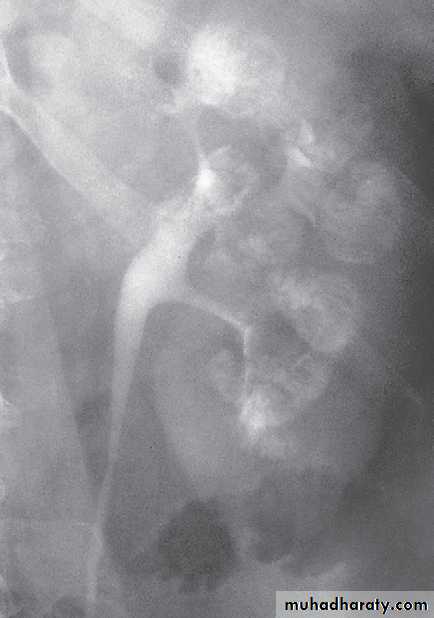

The diagnosis is made by ultrasound or IVU.

Contrast medium is seen to fill dilated or cystic tubules, which are sometimes calcified.

MSK. A, plain film shows medullary nephrolithiases. B, IVU 10-min, clusters of rounded densities in the papillae discrete linear opacities (paintbrush appearance).

MSK. IVUcontrast medium filling both the collecting system and cavities arising from collecting ducts, The cavities have been likened to bunches of grapes..